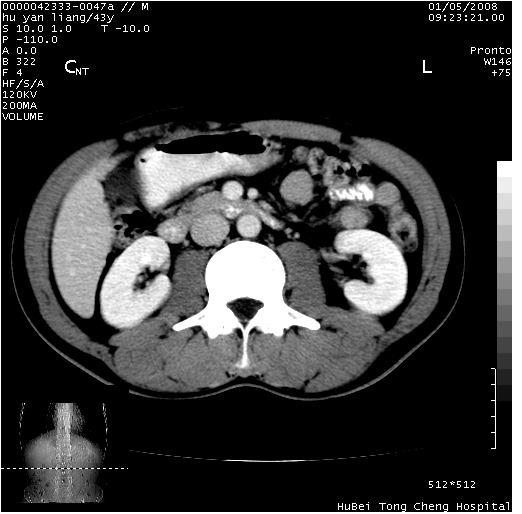

患者 男,43岁。右上腹不适1年余。既往有“肝右叶肝脓肿”病史,经保守治疗后痊愈。

b超提示:1)肝右叶肝内胆管结石。2)肝右叶占位性病变待排。

上中腹部ct轴位平扫+增强扫描(层厚10mm,螺距1.0,重建间隔10mm),图像如下:

肝右上叶偏后方较大团片状钙化灶,支持:肝脓肿后遗改变!

肝右叶后段团块状钙化灶,结合病史考虑肝脓肿痊愈后表现。